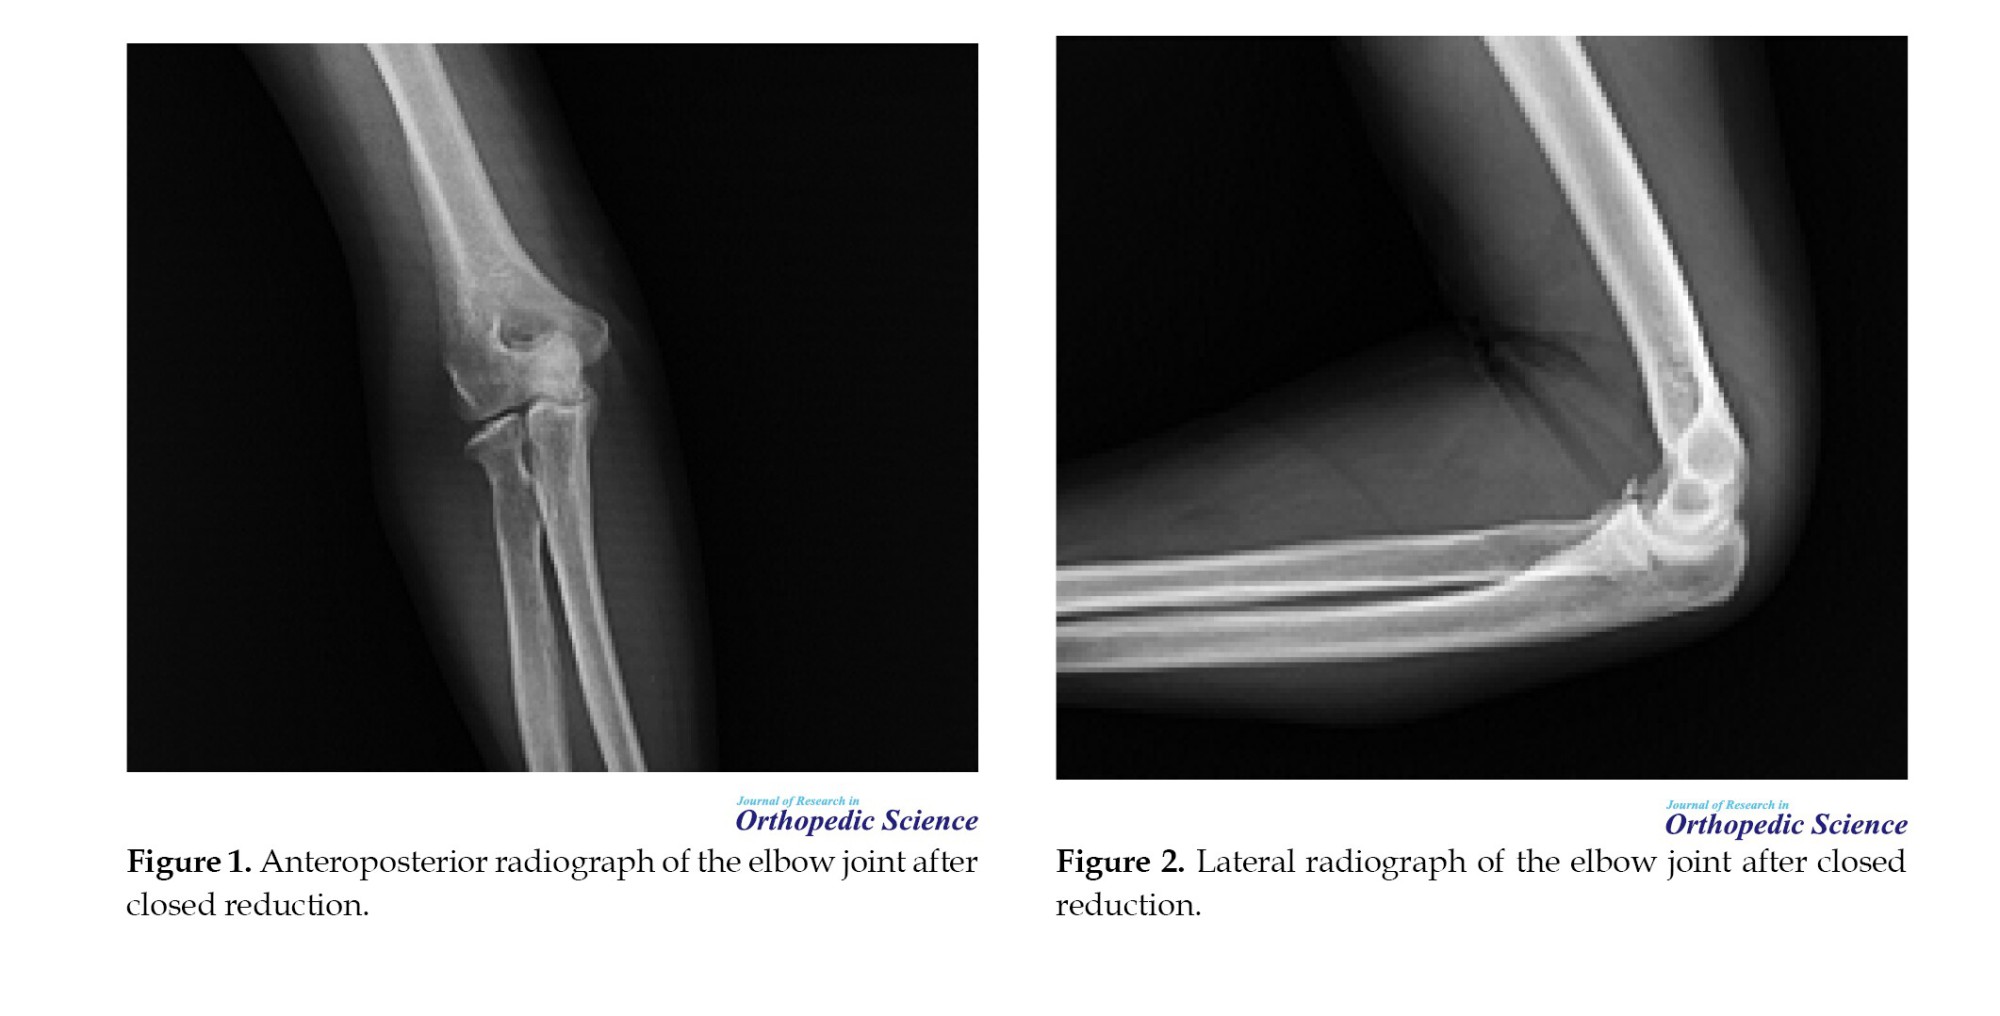

Patients were referred to physiotherapy for early active ROM exercises, with extension initially limited to 45 degrees and gradually increased weekly. Functional outcomes were assessed using the Mayo elbow performance index (MEPI) and the disabilities of the arm, shoulder, and hand (DASH) score. ROM was measured using a goniometer, and radiographic evaluation was performed to determine joint congruency, fracture :union:, and the presence of arthritis (Figures 3, 4, 5 and 6).